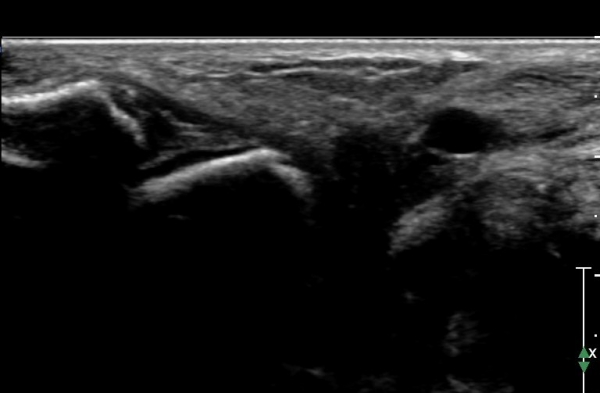

ÇϺΠ½ÅÀü ¶ì(inferior extensor retinaculum) ÀÇ frondiform Àδë Á¾´Ü¸é°Ë»ç¿¡¼­

frondiformÀδëÀÇ Àú¿¡ÄÚ ºÎÁ¾°ú °Å°ñÇÏ °üÀý °£°ÝÀÌ ¹ú¾îÁ® ÀÖ´Ù(»çÁø 8, 9).